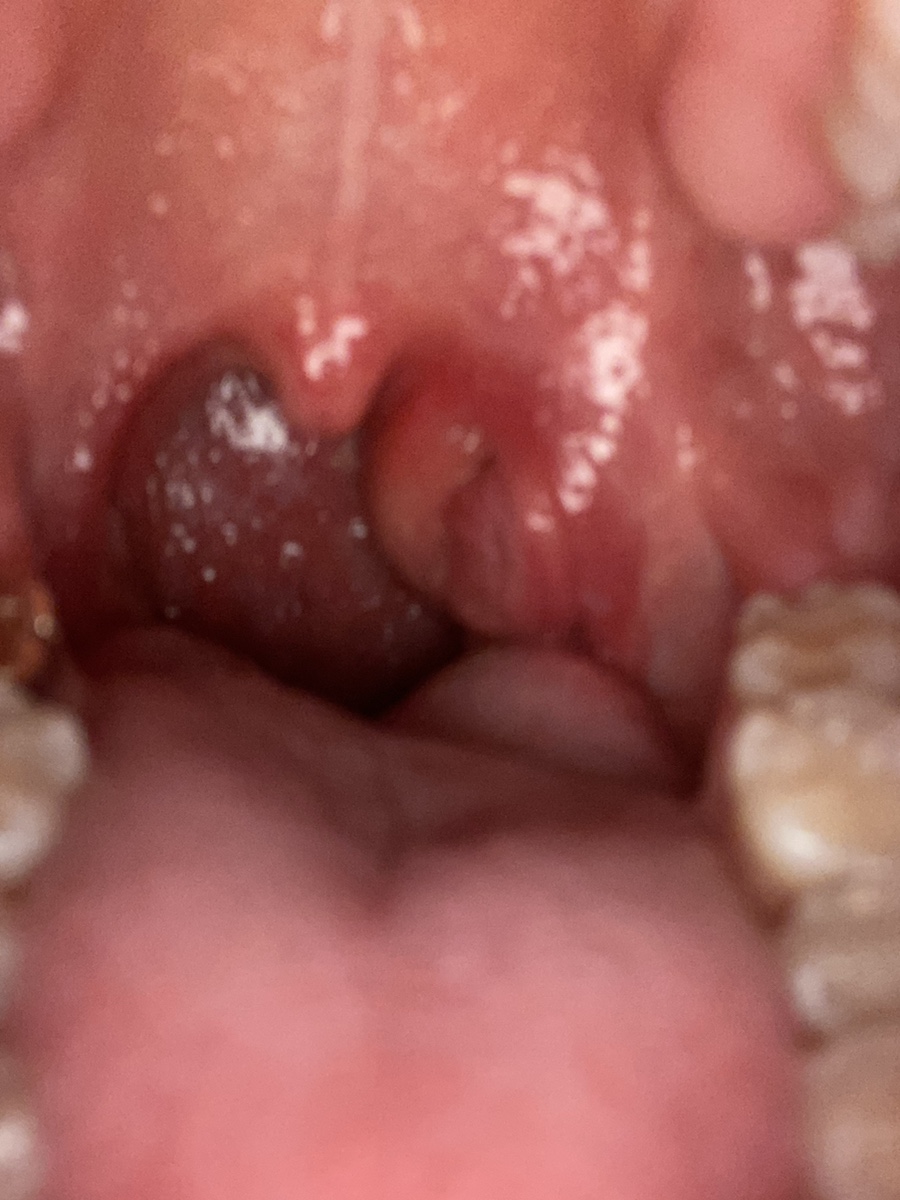

8/11 목요일 아침 8시경 편도선이 점점 인후편도선까지 붓는 것이 눈에 보였다.화요일부터는 아침 5~6시쯤 계속 목이 안좋아 잠에서 깼습니다.역시 숨통이 트이고 목이 건조하니까. 어쨌든 증상이 더 심해져서 다시 병원에 갔다.

괜찮을 것 같아서 운동도 가고 무리해서 그런지 자기 전에 편도를 다시 봤는데 목 편도선이 더 부어있었는데 어떡하지… 괜찮아질 것 같아서 자는 수밖에… 그리고 6월에 아팠던 것처럼 심하지도 않아서 밥도 먹고 물도 마시고 다 했다.조금 불편함이 있었지만 그래도…

금요일 새벽 5시에 또! 아파서 잠에서 깬 후 편도선이 빵빵하게 부어있는 모습… 차라리 빨리 농양이 쌓여 절개해 버리고 싶다고 생각한 지긋지긋한 편도염 농양만 빠지면 살만하니까..